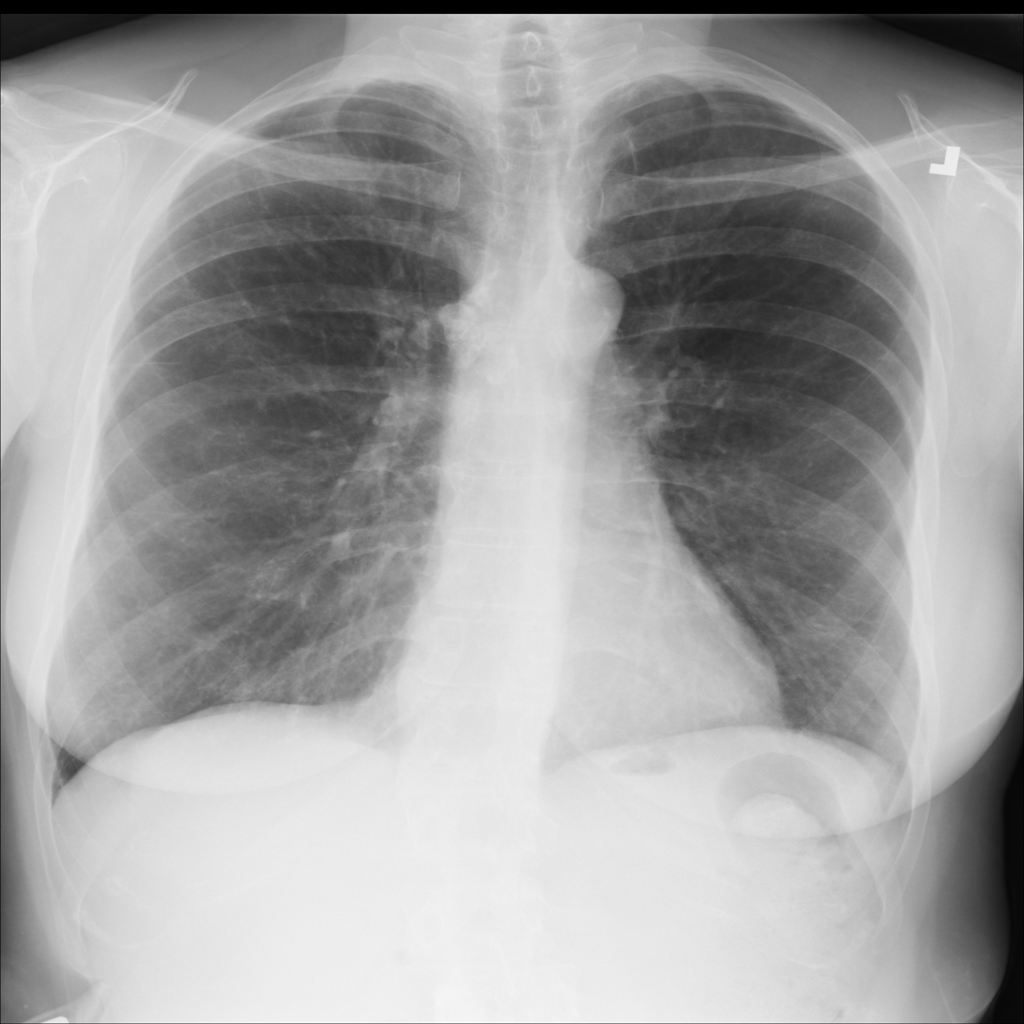

Showing up to 90 reference images for Fibrosis.

PAT-C77C · IMG-003Fibrosis

PAT-C77C · IMG-003

PA